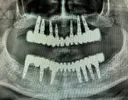

Implant Treatment